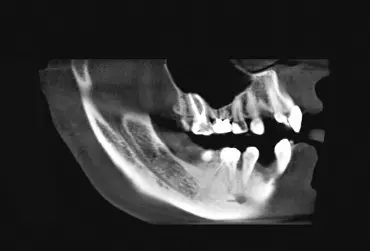

Obrazowanie za pomocą tomografii komputerowej efektu zabiegu augmentacji wyrostka zębodołowego po ekstrakcji zęba

Zapobieganie rozległym zabiegom augmentacyjnym należy rozpocząć jak najszybciej. Najlepiej zaraz po usunięciu zęba. Zrekonstruowanie niewielkich ubytków kostnych w blaszce policzkowej należy przeprowadzić poprzez odbudowę zębodołu. Można to przeprowadzić w technice socket preservation, w technice zastosowania kości własnej, poszerzenie i rozszczepienie kości, boczny czy pionowy przeszczep bloku kostnego oraz tzw. rekonstrukcją 3D. W jakim stopniu powiodła się ta rekonstrukcja, można się dowiedzieć z obrazowania przestrzennego, jakim jest tomografia komputerowa stożkowa zębów 3D (CBCT).